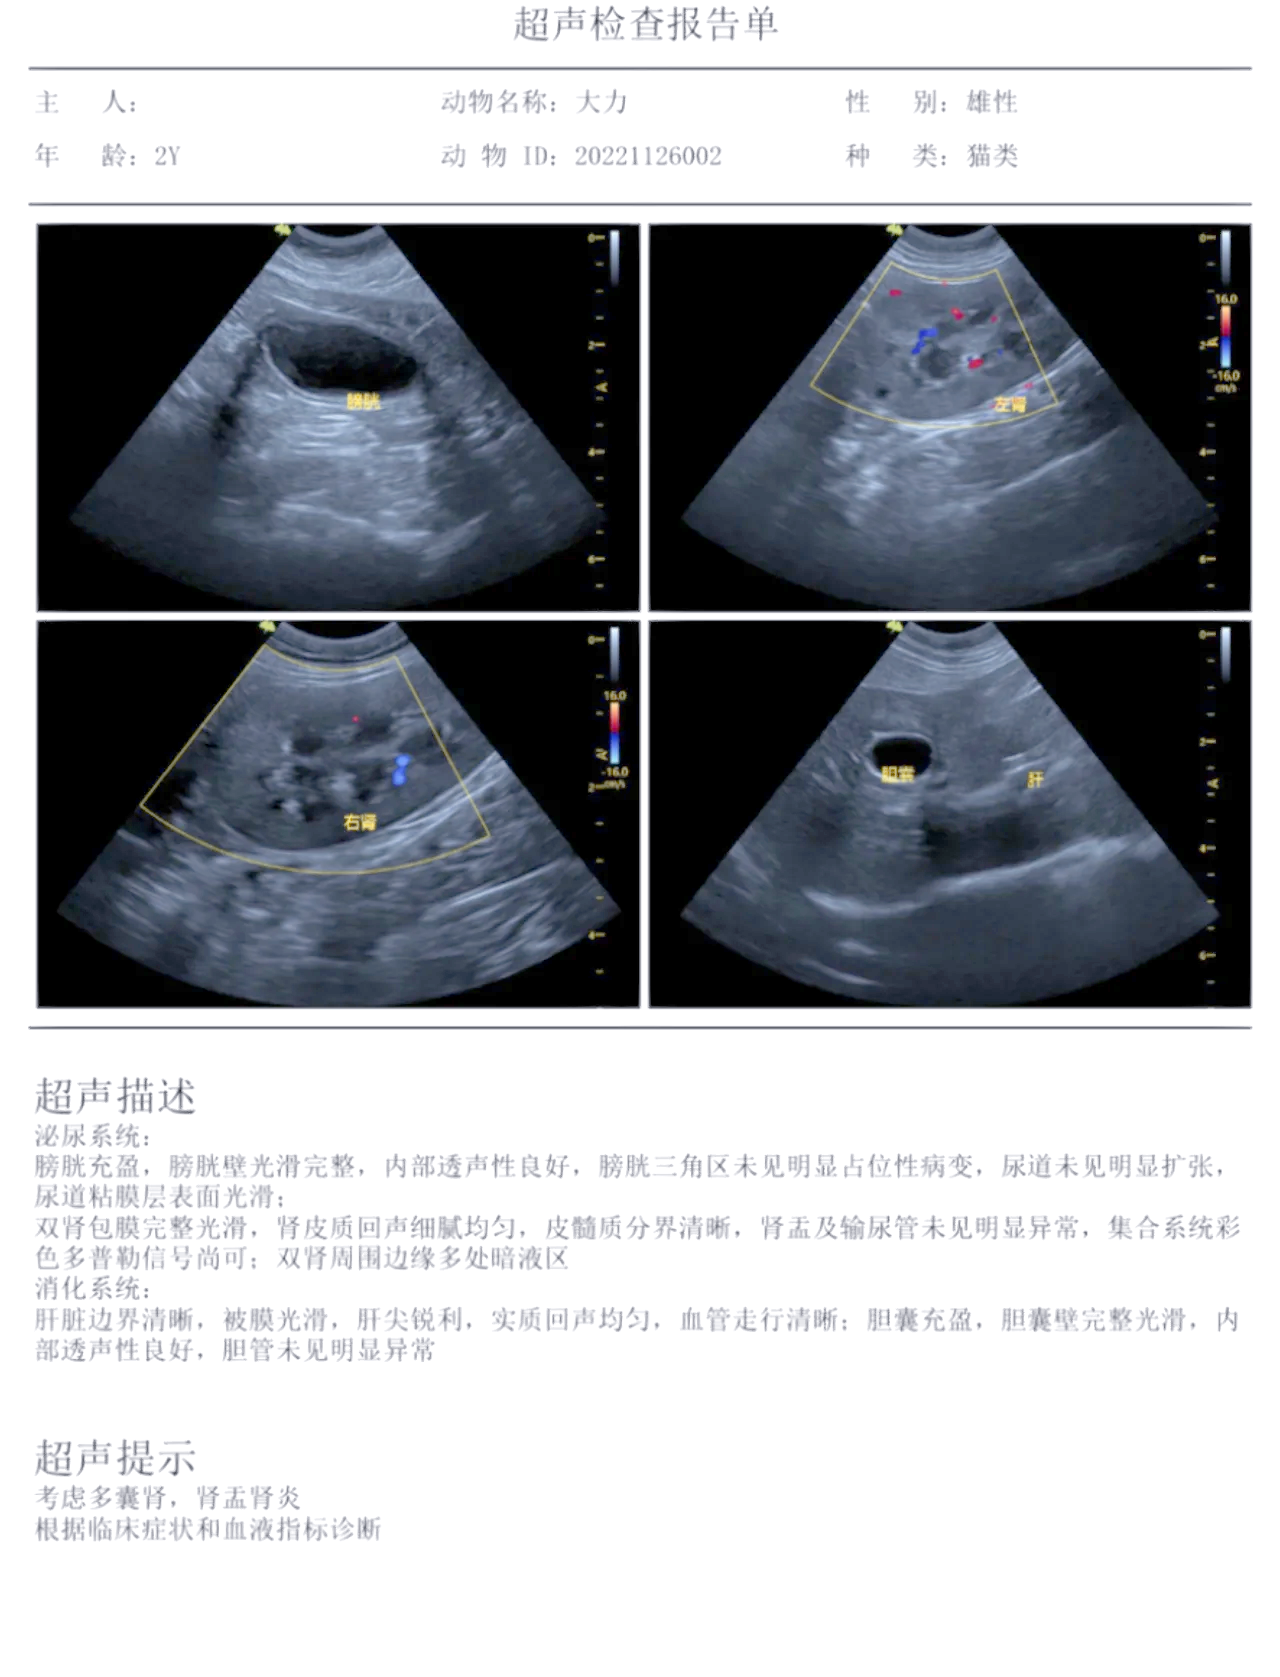

多囊肾最新治疗方法有哪些?

3手术治疗囊肿去顶减压术适用于直径较大或压迫肾实质的囊肿,通过切除囊肿顶部释放囊液,减轻对肾脏的压迫肾移植是终末期肾病患者的有效治疗手段,但需评估供体匹配度及术后免疫抑制治疗的风险4中医治疗中药治疗以辨证论治为核心,...